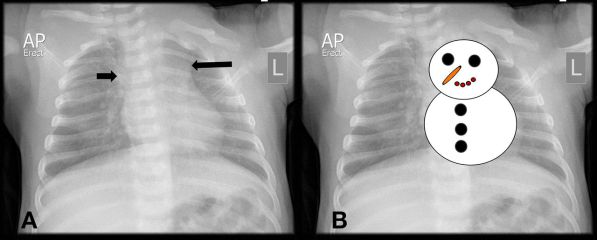

Snowman or Figure 8 sign on CXR is associated with this cardiac condition

TAPVR